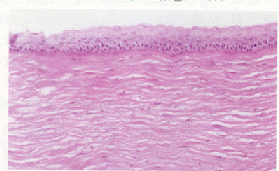

2.2 光镜观察 术后3天,角膜上皮细胞1层或2层覆盖切削区。术后30天,可见角膜上皮细胞增生,体积增大,细胞由正常的5层或6层增加到7层或8层。术后100天,角膜上皮细胞基本恢复正常。见图1~图4。

图1 正常兔角膜上皮细胞,基底细胞排列呈现整齐的栅状,HE染色,×200